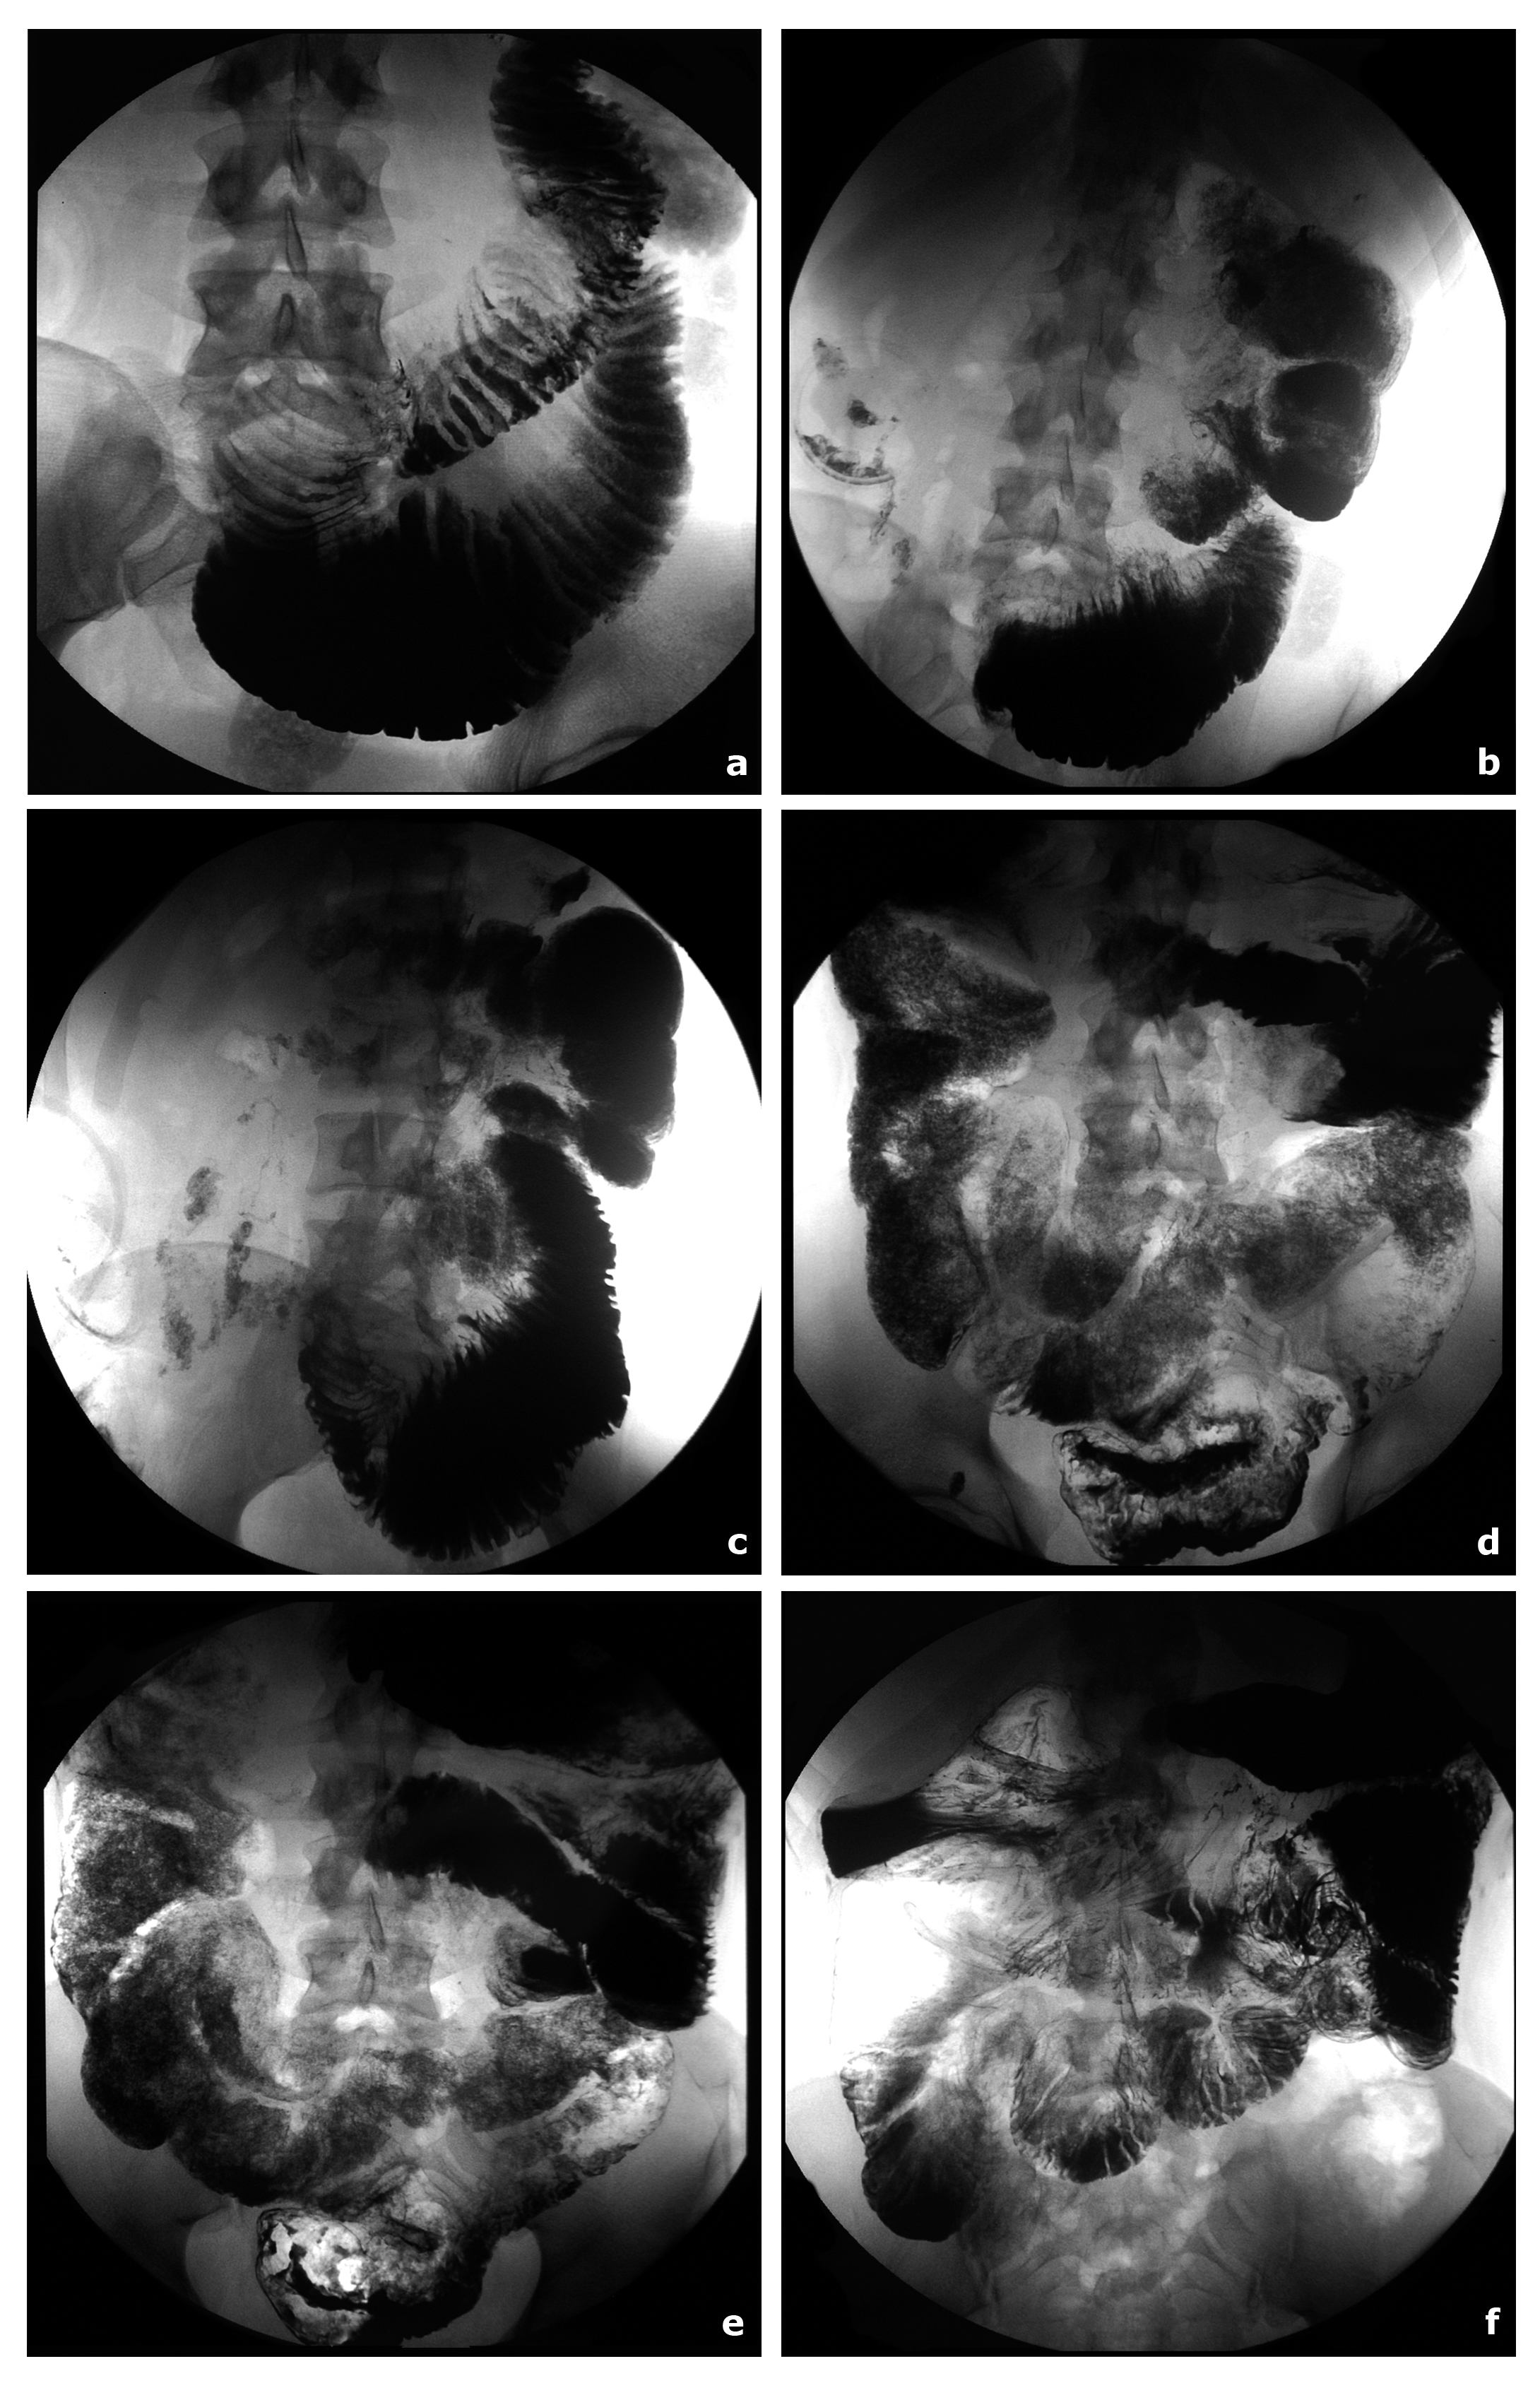

La displasia neuronal intestinal tipo B (DNIB) es una enfermedad poco frecuente debida a la hiperplasia del plexo submucoso parasimpático que cursa con alteración de la motilidad intestinal, ocasionando síntomas de estreñimiento y cuadros suboclusivos1. Es una enfermedad difícil de diagnosticar que requiere alta sospecha clínica y debería incluirse en el diagnóstico diferencial de los pacientes con cuadros suboclusivos de repetición con el fin de hacer un diagnóstico correcto temprano y evitar complicaciones derivadas de cirugías innecesarias que empeoran el pronóstico.

Se presenta el caso de un varón marroquí de 33 años que fue ingresado en nuestro hospital en 2 ocasiones un total de 11 meses, precisando durante 5 meses nutrición parenteral total (NPT). El análisis inmunohistoquímico de la boca de ileostomía y colostomía lleva al diagnóstico de DNIB. Dieciocho meses después, el paciente hace vida normal y ha recuperado los 25 kilos perdidos siguiendo las indicaciones dietéticas y con los suplementos enzimáticos.Descargas